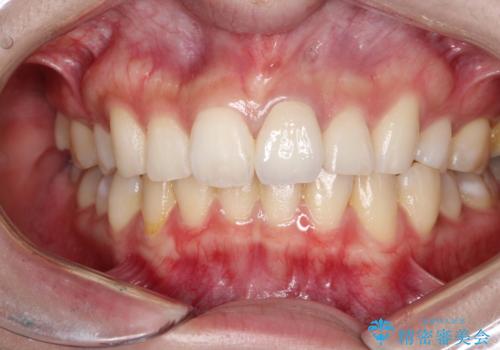

- 前歯が、ポロポロ欠けてくることを主訴で来院された女性です。

以前に根の治療しましたが、最近になって色なども気になり来院されました。

神経の治療をしている歯は、時間と共に色がどんどん変色していきます。

また、神経、血液供給がなくなってしまう影響から歯も脆くなっていってしまうため、歯が割れてしまうリスクもあります。